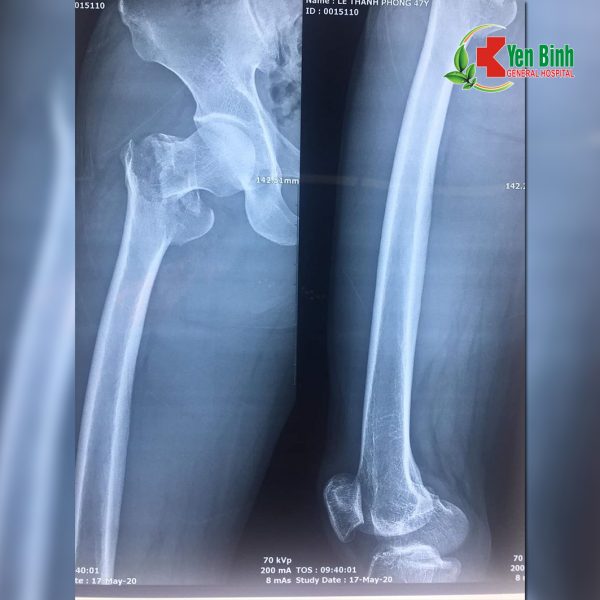

??⚕️?⚕️ Mới đây, bệnh viện Đa khoa Yên Bình đã tiến hành phẫu thuật cho bệnh nhân bị gãy cổ xương đùi phải. Bệnh nhân Lê Thanh P, 47 tuổi, địa chỉ tại xã Úc Kỳ, huyện Phú Bình. Bệnh nhân bị ngã từ độ cao 3m, đập hông xuống đất, nhập viện tại Bệnh viện Đa Khoa Yên Bình. Kết quả chụp X-quang tại bệnh viện cho thấy ông P bị gẫy kín cổ xương đùi chân phải di lệch, gẫy đầu dưới xương quay tay phải, có chỉ định phẫu thuật.

Hình ảnh chụp Xquang của bệnh nhân (Nguồn hình do các bác sỹ Bệnh viện Đa khoa Yên Bình cung cấp)